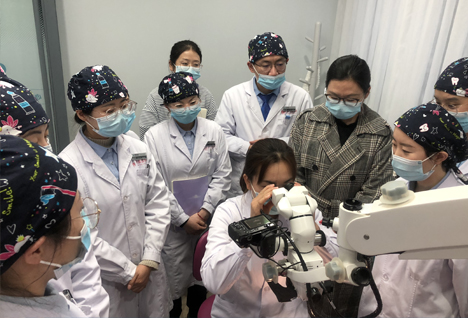

集团医疗设备先进完备,拥有多台Planmeca口腔CT、YSGG水激光治疗仪、3Shape全真三维口腔扫描仪、iTero正畸诊断扫描仪、Zumax牙科显微镜、德国CEREC全系列CAD/CAM等先进的诊疗设备

隐适美公司iTero口腔扫描仪培训 显微镜临床操作和使用技巧培训

显微镜临床操作和使用技巧培训 嵌体的修复方式及粘接步骤培训

舒适化口腔治疗镇静技术 西默显微镜

西默显微镜 啄木鸟wooddeckrr超声骨刀